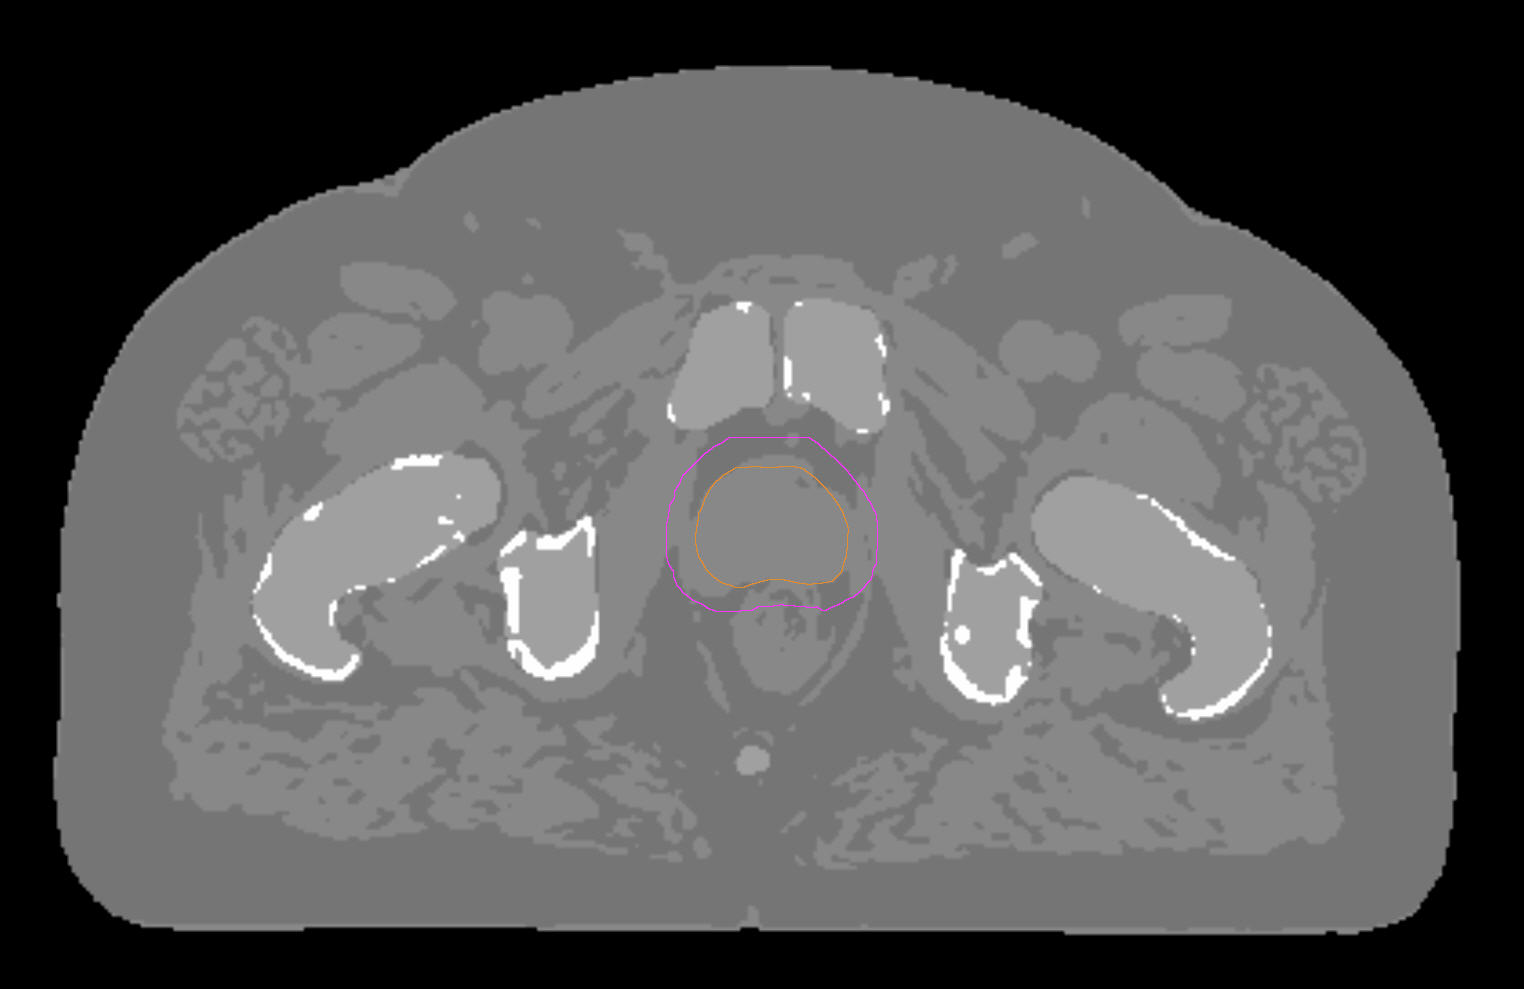

77-year-old male with prostate cancer cT3aN0M0, Gleason 8 and PSA 52 µg/L referred to androgen deprivation and radiation therapy with a prescribed dose of 50 Gy to the pelvic lymph node regions and 76 Gy to the prostate. Patient underwent MRI on Ingenia MR-RT 1.5T using FlexCoverage Anterior Coil in combination with the integrated Posterior Coil. Dose planning was performed on MRI imaging data.